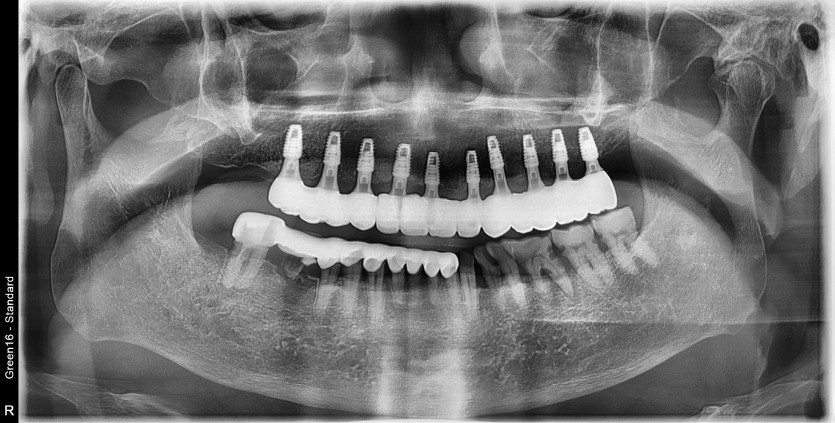

상악 전체 임플란트 증례입니다.

10개의 임플란트로 완성하였습니다.